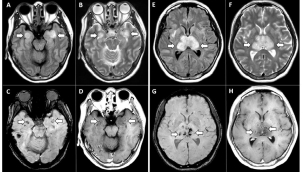

Covid-19 beynin küçülmesine neden oluyor -